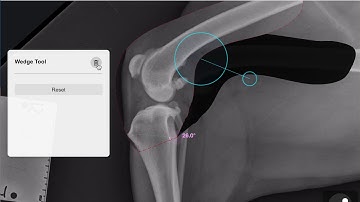

8- Circle tool and Common Tangent in vPOP-pro !